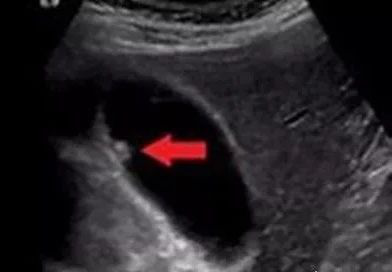

家恩德仁表示,胆囊息肉医学上称之为胆囊息肉样病变,是胆囊壁向胆囊腔内突出或隆起的局限性息肉样病变的总称。虽然都叫“胆囊息肉”,但它们还是分做“真性息肉”和“假性息肉”。

单发性胆囊息肉

多发性胆囊息肉